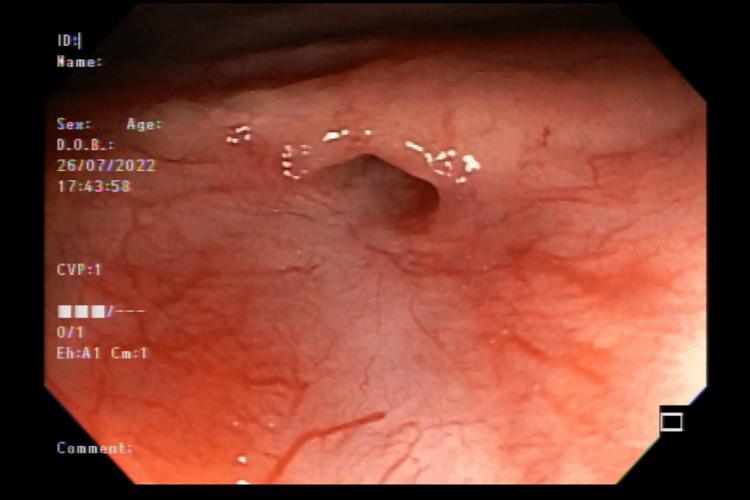

We present a case of a 68-year-old man with a rectourethral fistula (RUF) successfully treated with a unique endoscopic approach using the Padlock Clip system (Steris, Basingstoke, UK). This is a complex case of a patient who, after radical prostatectomy, continued to show several complications, including fistulas and relapses. Our work aims to enhance the literature with our technique and to help the scientific community in future RUF cases. Our case stands out because this therapeutic approach has not yet been described in the literature as a possible endoscopic treatment of RUF. Therefore, our topic description is essential to assist future similar cases.

我们报告了一例68岁男性直肠尿道瘘(RUF)患者,采用独特的内镜方法,使用挂锁夹系统(英国贝辛斯托克的史赛克公司)成功治疗。这是一例复杂病例,患者在根治性前列腺切除术后持续出现多种并发症,包括瘘管和复发。我们的工作旨在通过我们的技术丰富文献,并在未来RUF病例中帮助科学界。我们的病例很突出,因为这种治疗方法在文献中尚未被描述为RUF的一种可能的内镜治疗方法。因此,我们对该病例的描述对于协助未来类似病例至关重要。